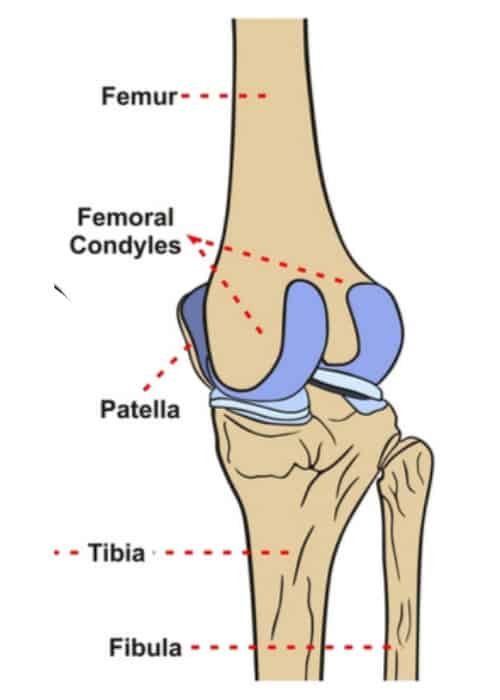

Femoral condyles

rounded ends of the thigh bone at the knee

coated with a smooth layer of hyaline cartilage